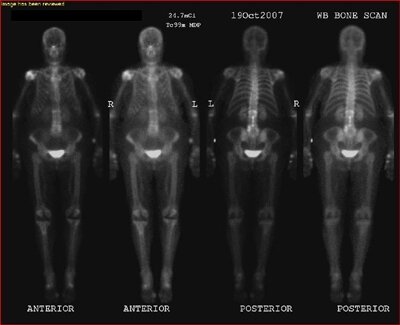

Médecine nucléaire

L'imagerie fonctionnelle in vivo qui consiste en l'administration d'un traceur radioactif au patient permettant sa détection externe. Ce sont les scintigraphies (émission de rayonnements gamma) ou les TEP (Tomographies d'émission de positons).

Examen de médecine nucléaire

La médecine nucléaire se distingue de la plupart des autres techniques d'imagerie médicale en ce qu'on obtient des images physiologiques plutôt qu'anatomiques. Des molécules dont le comportement biologique est connu sont introduites dans le corps du patient de la façon appropriée au test en cours: injecté, avalé, inhalé etc. Leur comportement est alors étudié par le biais de l'imagerie par émission. Les images obtenues peuvent êtres statiques mais, contrairement à la majorité des modalités d'imageries par transmission, il est souvent possible d'obtenir des images dynamiques.

Certaines techniques permettent une reconstruction dynamique (mouvement) par superposition d'images prises à des temps différents (coeur). La médecine nucléaire se prête à la quantification.La médecine nucléaire se distingue de la plupart des autres techniques d'imagerie médicale en ce qu'on obtient des images physiologiques plutôt qu'anatomiques. Des molécules dont le comportement biologique est connu sont introduites dans le corps du patient de la façon appropriée au test en cours: injecté, avalé, inhalé etc. Leur comportement est alors étudié par le biais de l?imagerie par émission. Les images obtenues peuvent êtres statiques mais, contrairement à la majorité des modalités d'imageries par transmission, il est souvent possible d'obtenir des images dynamiques.